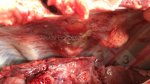

Atlas de patologia